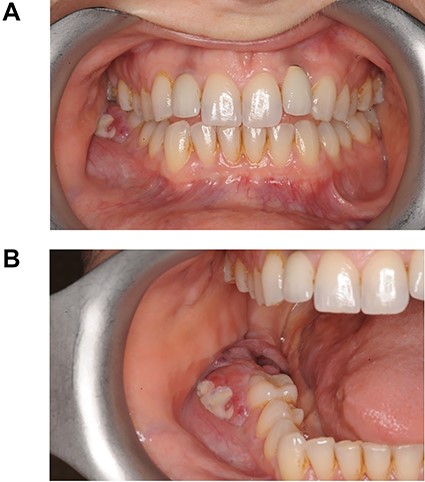

At her OMFS appointment, the consultant was concerned by the abnormal appearance of the extraction site intraorally, combined with the evolving systemic symptoms (Figs 2–4). Urgent magnetic resonance imaging (MRI) head and neck (Figs 5 and 6) and computerized topography (CT) mandible scans were requested and completed in an extremely short time frame.

(A) and (B) Photos showing the site of Burkitt’s tumour infiltrating the oral mucosa and extraction site of LR7 prior to incisional biopsies taken by the OMFS team.